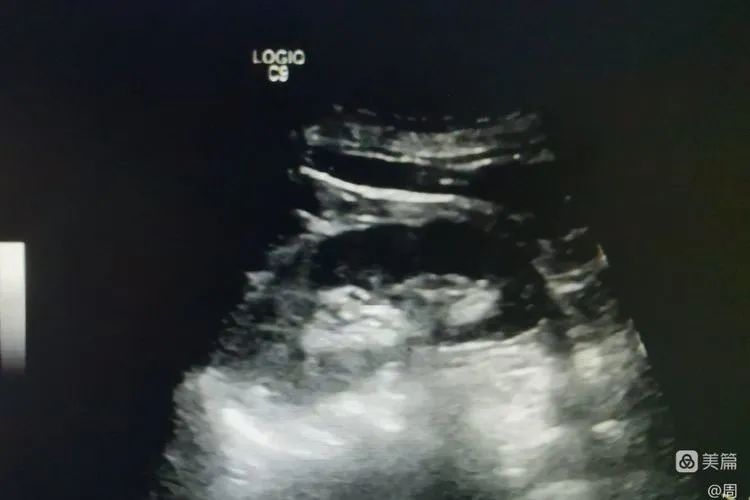

术前囊肿大小

7月14日,龙泉驿区中医医院超声科成功实施首例肾囊肿硬化治疗。患者男,57岁,因左侧膝关节滑膜炎入院做常规彩超检查,发现大小约4.5cmx5.0cm的右肾囊肿,肾实质受压,囊肿无分隔,初步考虑为单纯性囊肿。